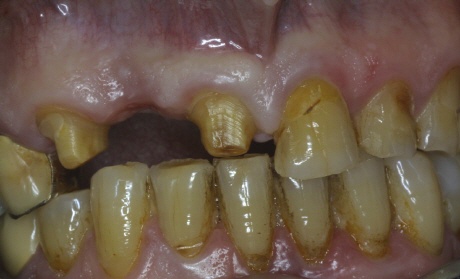

Beschliffene Zähne = Verletzte Zähne

Für einen fehlenden Zahn müssen zwei gesunde Zähne beschliffen werden. Zum Größenvergleich: Der rechte beschliffene Zahn war vor dem Beschleifen mal genauso groß wie der Zahn rechts neben ihm! Mit Hilfe von Implantaten läßt es sich fast immer vermeiden, dass gesunde Zähne beschädigt werden. Sie sind daher medizinisch in der Regel das Mittel der Wah.l